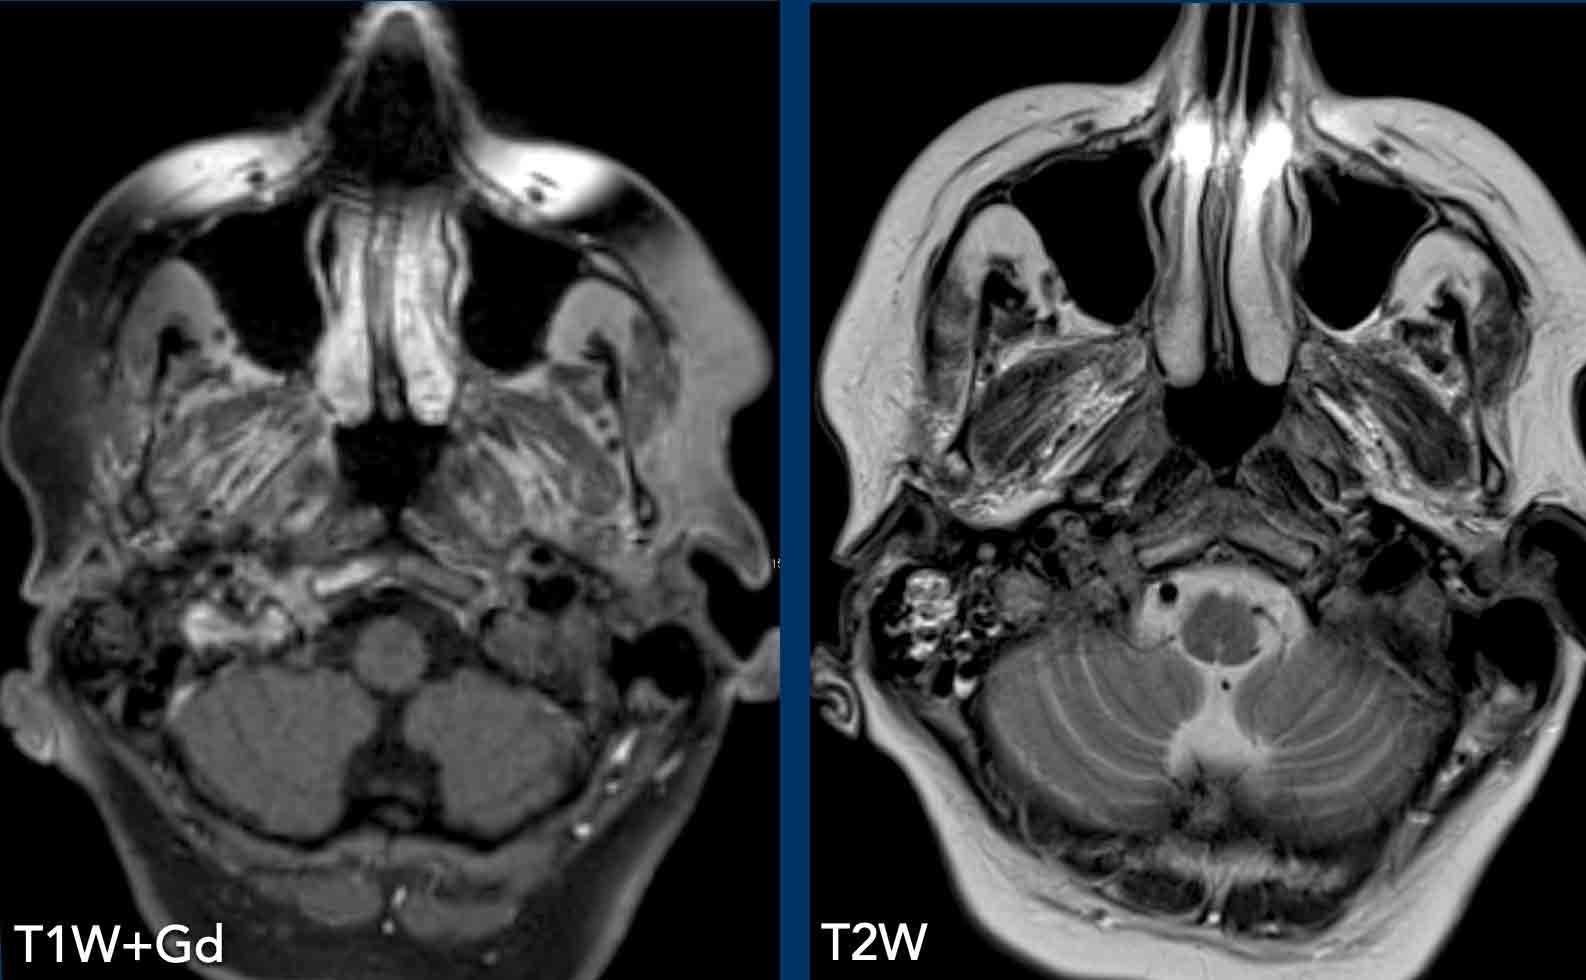

Những hình ảnh này của một người đàn ông 78 tuổi

được biết là có ung thư biểu mô tế bào vảy ở sàn miệng và than phiền về nhìn đôi.

Khi khám thực thể, bệnh nhân mất định hướng và có

rối loạn vận ngôn và hội chứng Horner.

Dựa trên những phát hiện này, chúng tôi cho rằng hội chứng Horner là

do nguyên nhân trung ương.

Hình ảnh

T1 MPRAGE 3D cho thấy một tổn thương ngấm thuốc dạng vòng nhẫn lớn ở vùng đồi thị bên phải và một tổn thương thứ hai ở bán cầu não phải.

Kết luận

Di căn của ung thư biểu mô tế bào vảy.

Thông thường các ung thư biểu mô này không di căn dễ dàng như vậy.

Ở các tầng khác có nhiều di căn hơn (vòng tròn).

Hình minh họa cho thấy mức độ của bệnh lý.